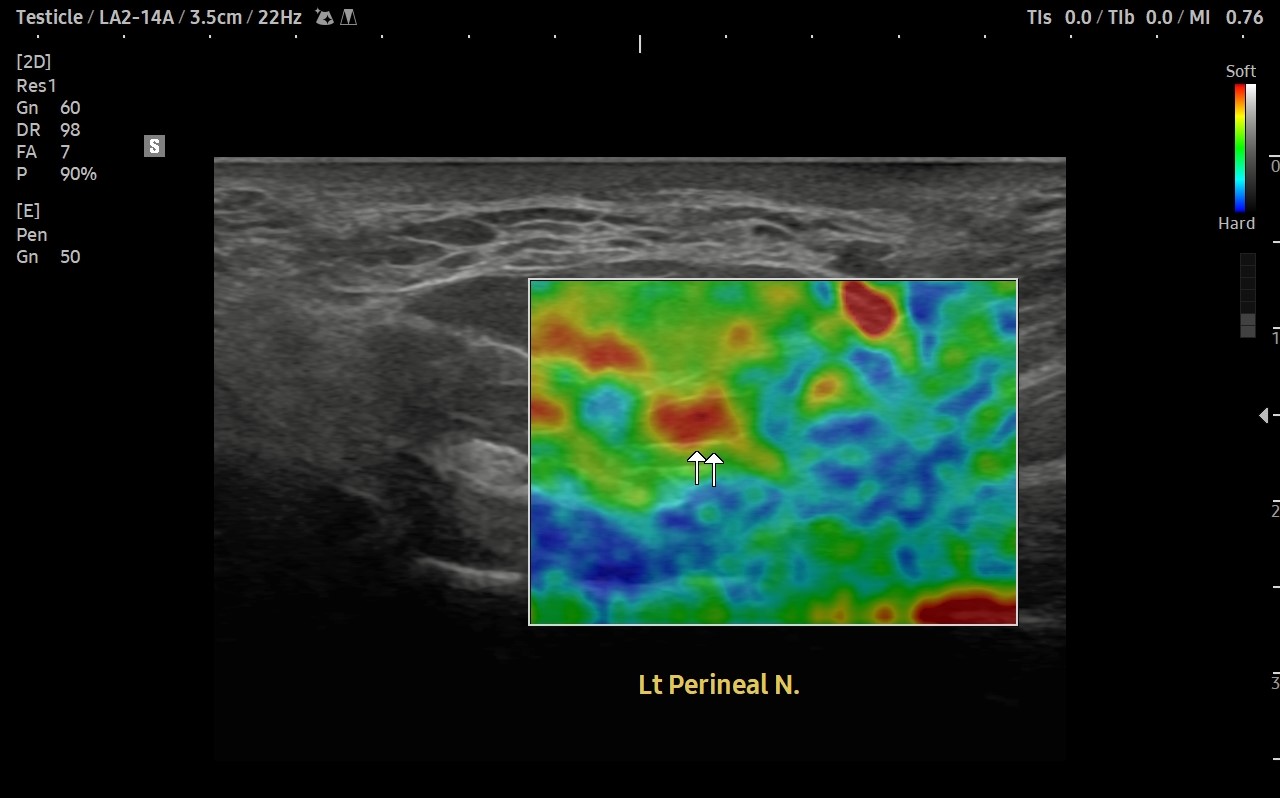

[치료 전]

[치료 후]

- 치료횟수 : 40 회